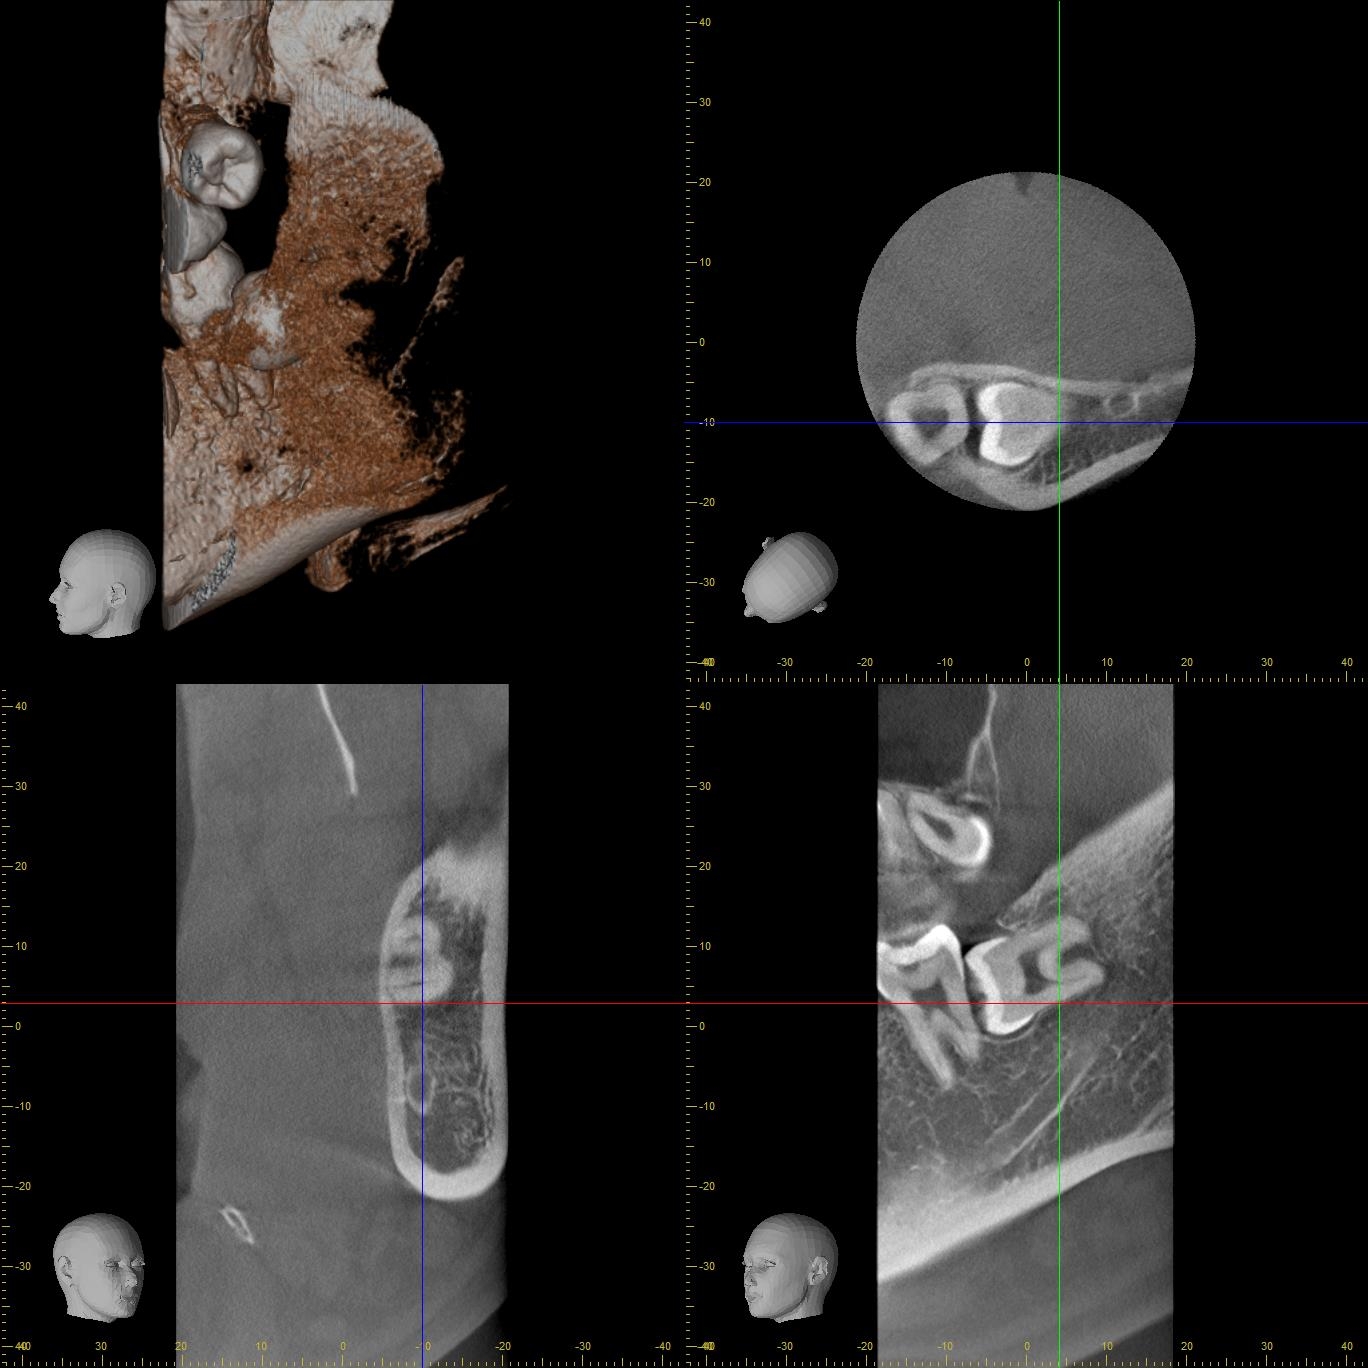

術前CT写真 (左)

術前CT写真

CT画像で状態を確認し、親知らずの歯根の曲がり具合や歯根の太さ、

下の親知らずの場合は下歯槽管神経との距離、

位置関係や骨の厚みなどを確認します。

下歯槽神経を傷をつけないように注意が必要です。

この場合、神経との距離を測り慎重に抜歯しないといけません。